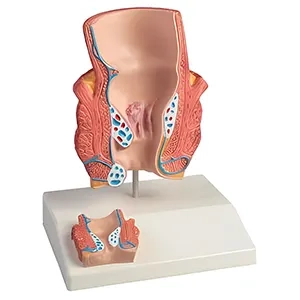

مولاژهای پاتولوژیک: این مدلها تغییرات بیماریها و اختلالات مختلف را نمایش میدهند و به مطالعه و آموزش بیماریها و شرایط غیرطبیعی بدن کمک میکنند.

ماکتهای پاتولوژیک: این مدلها تغییرات بیماریها و اختلالات را شبیهسازی میکنند. آنها میتوانند به بررسی و آموزش بیماریهای مختلف، تومورها، عفونتها و آسیبها کمک کنند.

- ماکتهای پاتولوژیک: برای شبیهسازی بیماریها و اختلالات.

مولاژهای پزشکی شامل انواع مختلفی از ابزارهای آموزشی هستند که به نمایش قسمتهای مختلف بدن انسان، مانند قلب، کبد، و سیستمهای دیگر میپردازند. این مولاژها میتوانند به صورت مدلهای ساده یا پیچیده و با جزییات دقیق طراحی شوند تا به کاربر کمک کنند ساختارهای داخلی بدن را بهتر بشناسد و تفاوتهای آناتومیکی را درک کند.